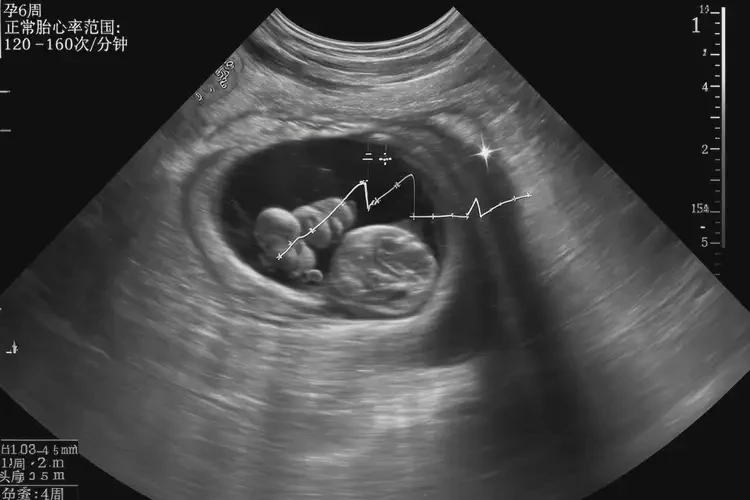

孕6周胎心率77寶寶還能要嗎

胎心率77次/分鐘在孕6周時(shí)并不理想,但不能僅憑此數(shù)值判斷寶寶是否能要。

胎心率是評(píng)估胎兒健康狀況的重要指標(biāo)之一,正常情況下,孕6周的胎心率應(yīng)在100-120次/分鐘之間。胎心率受多種因素影響,包括測(cè)量時(shí)間、胎兒活動(dòng)狀態(tài)以及孕婦自身狀況等。單次測(cè)量結(jié)果并不能完全代表胎兒的健康狀況。

• 孕6周:100-120次/分鐘

• 孕中期及晚期:120-160次/分鐘